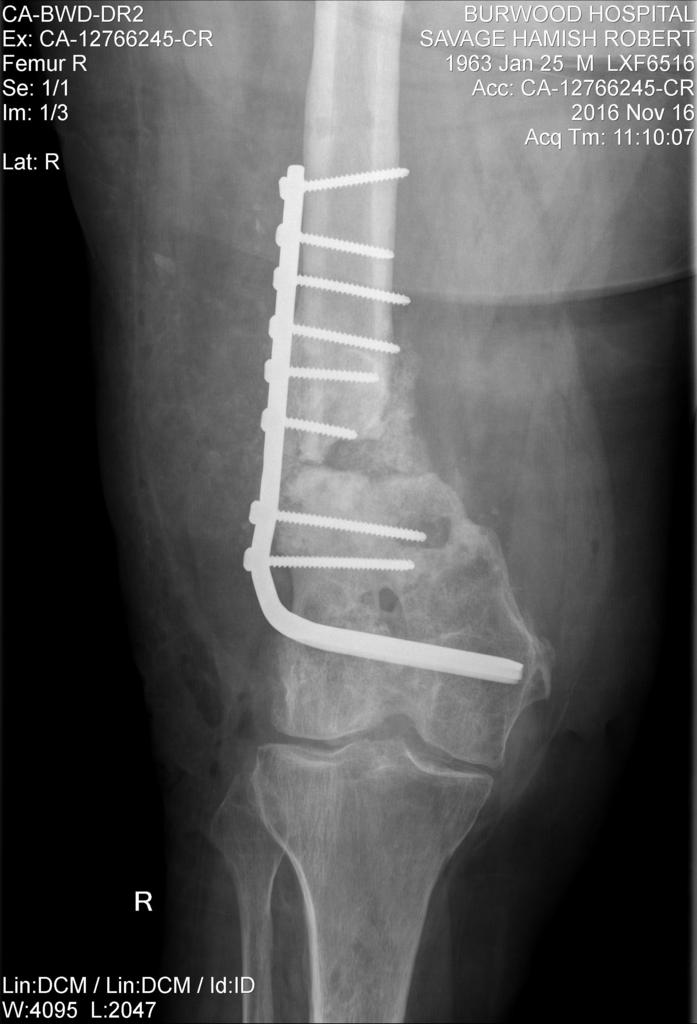

The latest attempt to stick my leg back together................ looks like a bit of old curtain rail